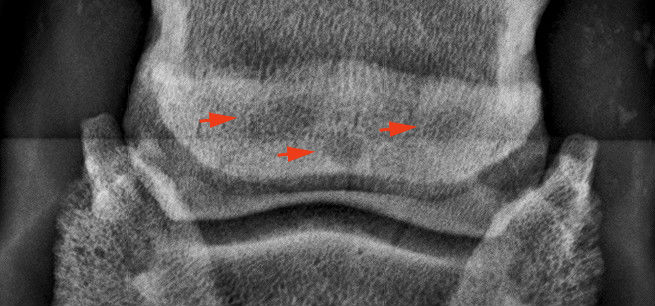

Három ciszta a nyírcsont állományában.

Kitágult csatornák (vékony nyilak) és oldódás a csont kéregállomáányában 8 vastag nyíl).